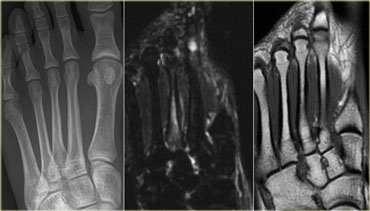

Stress fracture: Normal radiograph, while STIR image already shows a high signal intensity of the bone marrow Stress fracture: Normal radiograph, while STIR image already shows a high signal intensity of the bone marrow

On the left a 28-year old female with recent onset of pain over a region of the 2nd metatarsal bone.

At presentation, the radiograph was negative for fracture of the second metatarsal bone.

An MRI STIR (Short TI Inversion Recovery)sequence showed a high signal intensity of bone marrow and the surrounding soft tissue, indicating bone marrow edema as a result of a stress fracture.

Radiograph, STIR and T1WI of grade 3 stress fracture of 3rd metatarsal. Radiograph, STIR and T1WI of grade 3 stress fracture of 3rd metatarsal.

STIR (short tau inversion recovery), T1-weighted (T1WI) and T2-weighted images (T2WI) are used for characterization and grading.

Grading is based on signs seen at MRI:

1. mild - moderate periosteal edema on STIR, no marrow changes

2. moderate - severe periosteal edema on STIR + marrow changes on T2WI

3. 2 + marrow changes on T1WI

4. fracture line visible

On the left a 22-year old female, a professional athlete with a recent onset of forefoot pain, persisting after training.

At presentation MRI showed a high signal on the STIR- and a low signal on T1WI (i.e. grade 3 stress fracture).